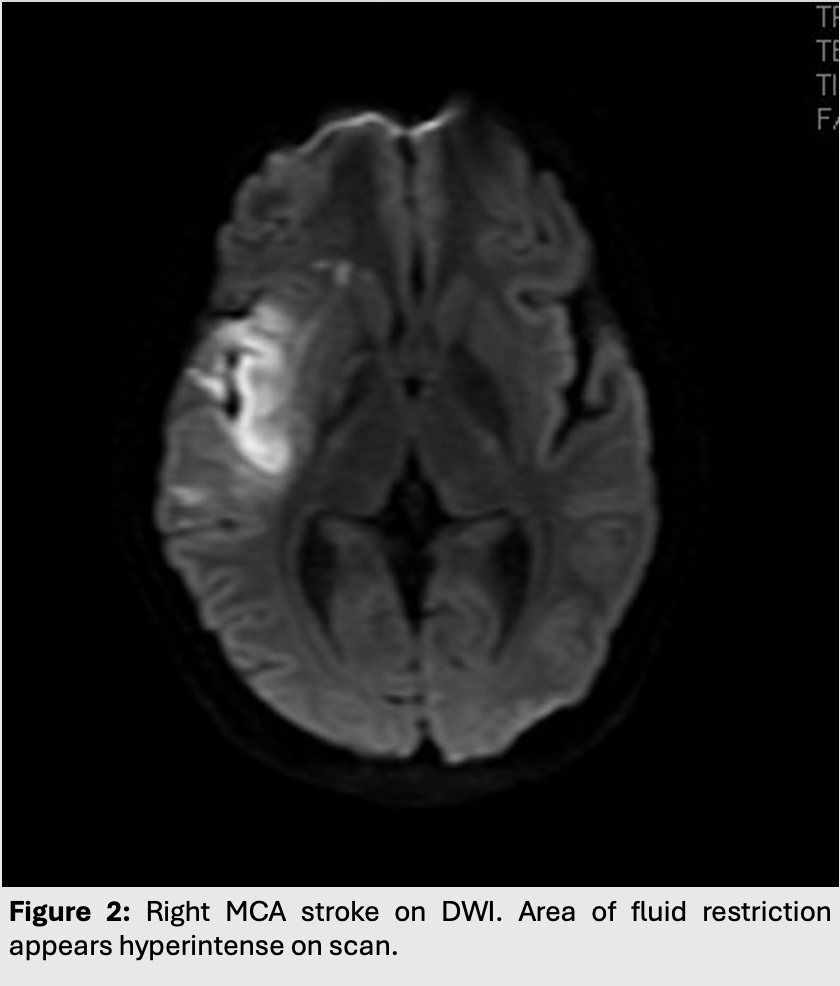

Figure 2: Right MCA stroke on DWI. Area of fluid restriction appears hyperintense on scan.

• However, it only takes between 10 to 60 minutes for and acute MCA infarct to be seen on DWI.

• Cortical edema takes at least 3 hours before it can be seen on T2/FLAIR (hyperintense with cortical thickening and loss of grey-white junction differentiation).